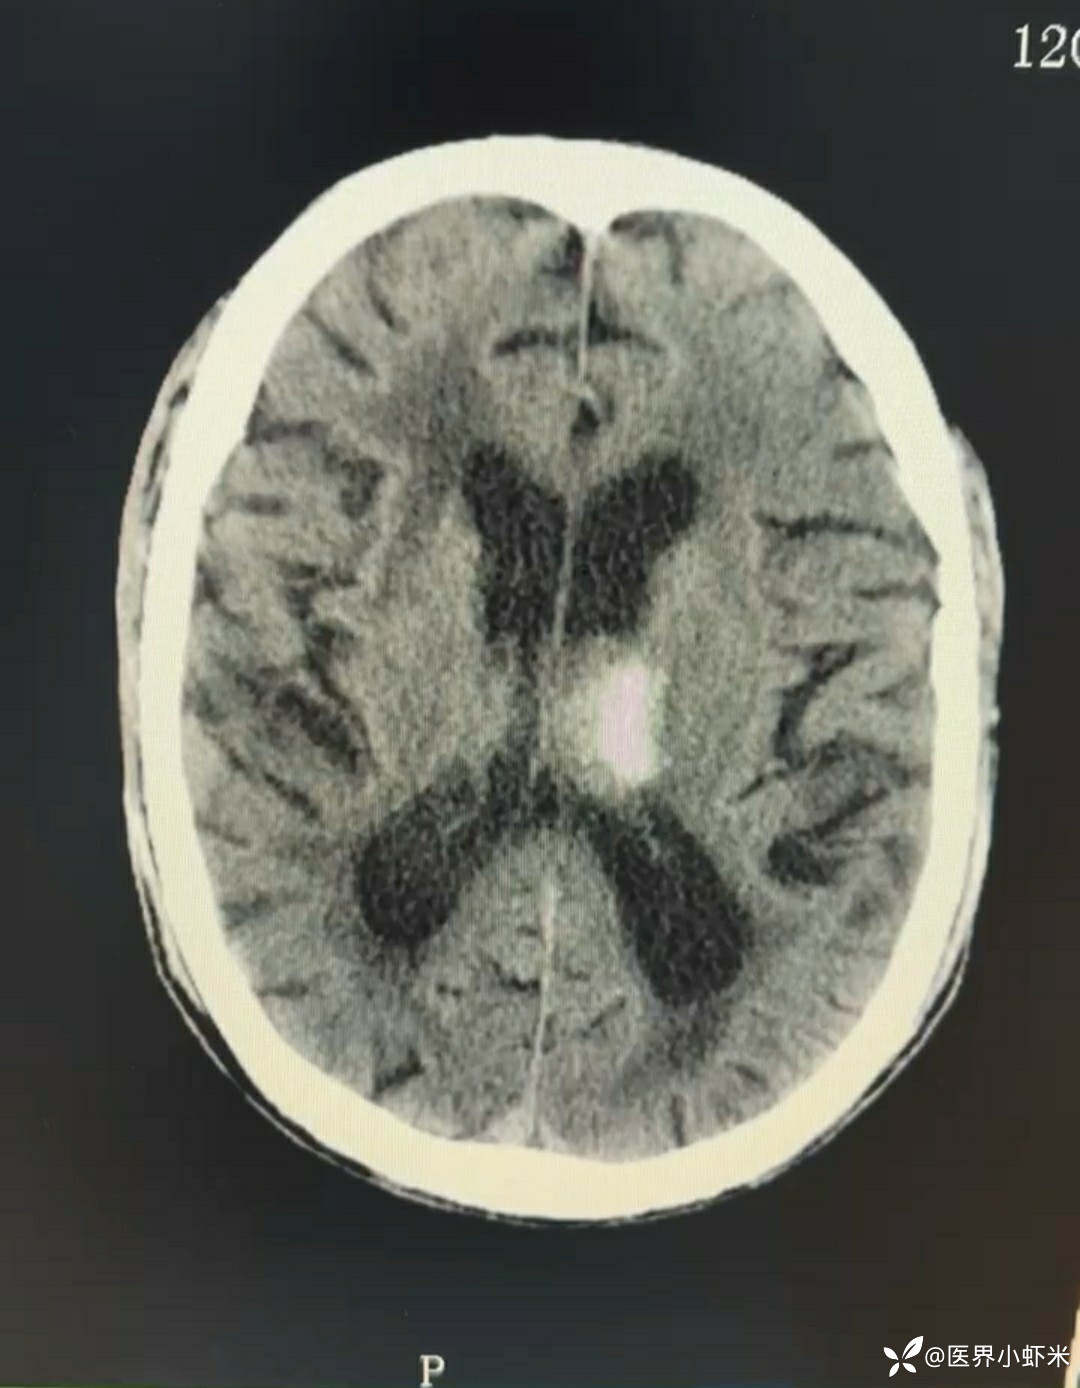

目前考虑:1.中央型肺癌伴2.肝继发恶性肿瘤?2.左丘脑继发恶性肿瘤?3.左丘脑出血?4.肾功能不全5.肝功能异常6右肾萎缩7.肺部感染8.慢性阻塞性肺病7.高血压3级(极高危)。